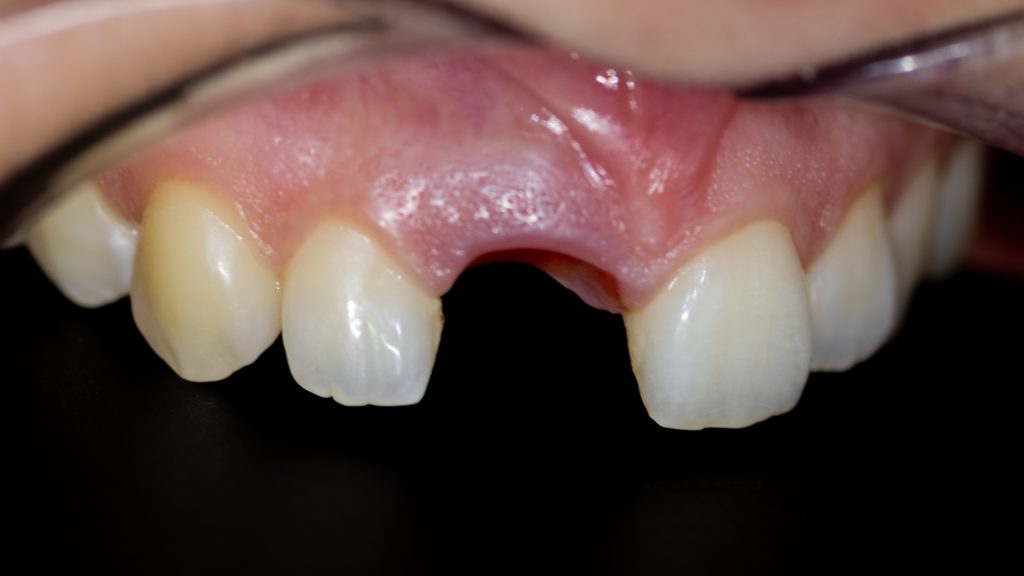

after initial healing